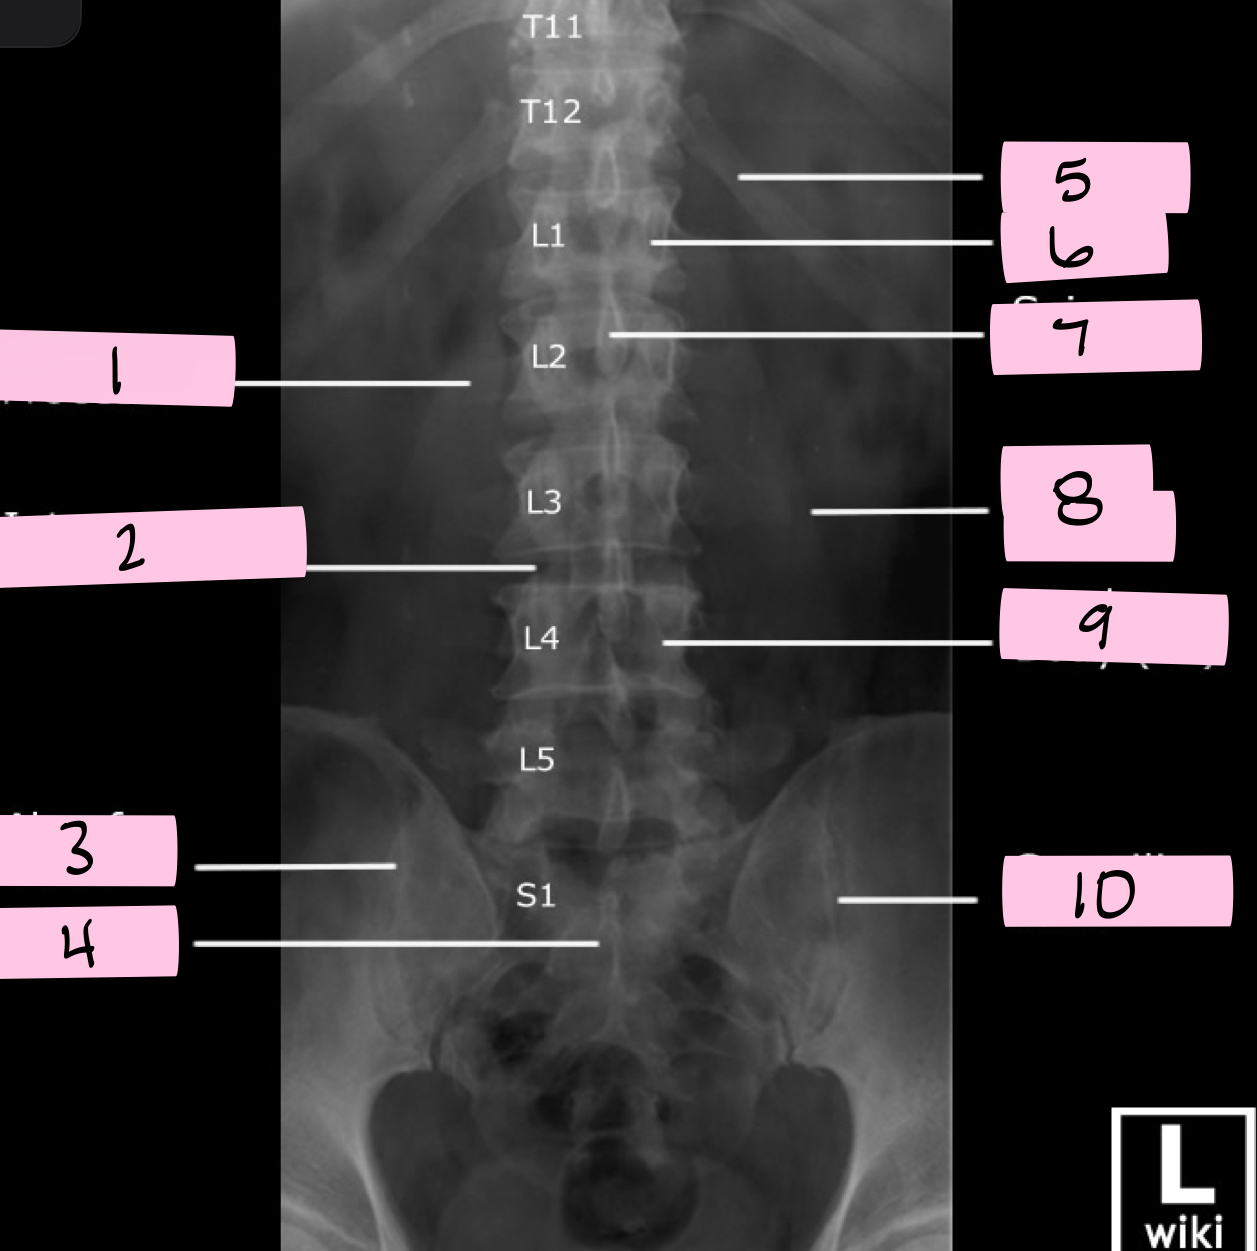

What is 1 pointing to?

Transverse process

What is 2 pointing to?

Intervertebral disk

What is 3 pointing to?

Ala of sacrum

What is 4 pointing to?

Sacrum

What is 5 pointing to?

12th Rib

What is 6 pointing to?

Pedicle

What is 7 pointing to?

Spinous process

What is 8 pointing to?

Psoas muscle

What is 9 pointing to?

Lumbar body (L4)

What is 10 pointing to?

Sacroiliac joint